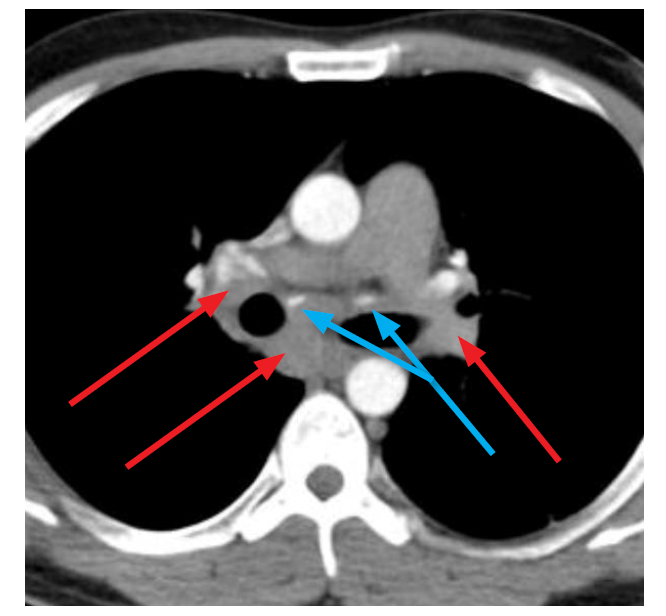

What is the red arrows?

PE